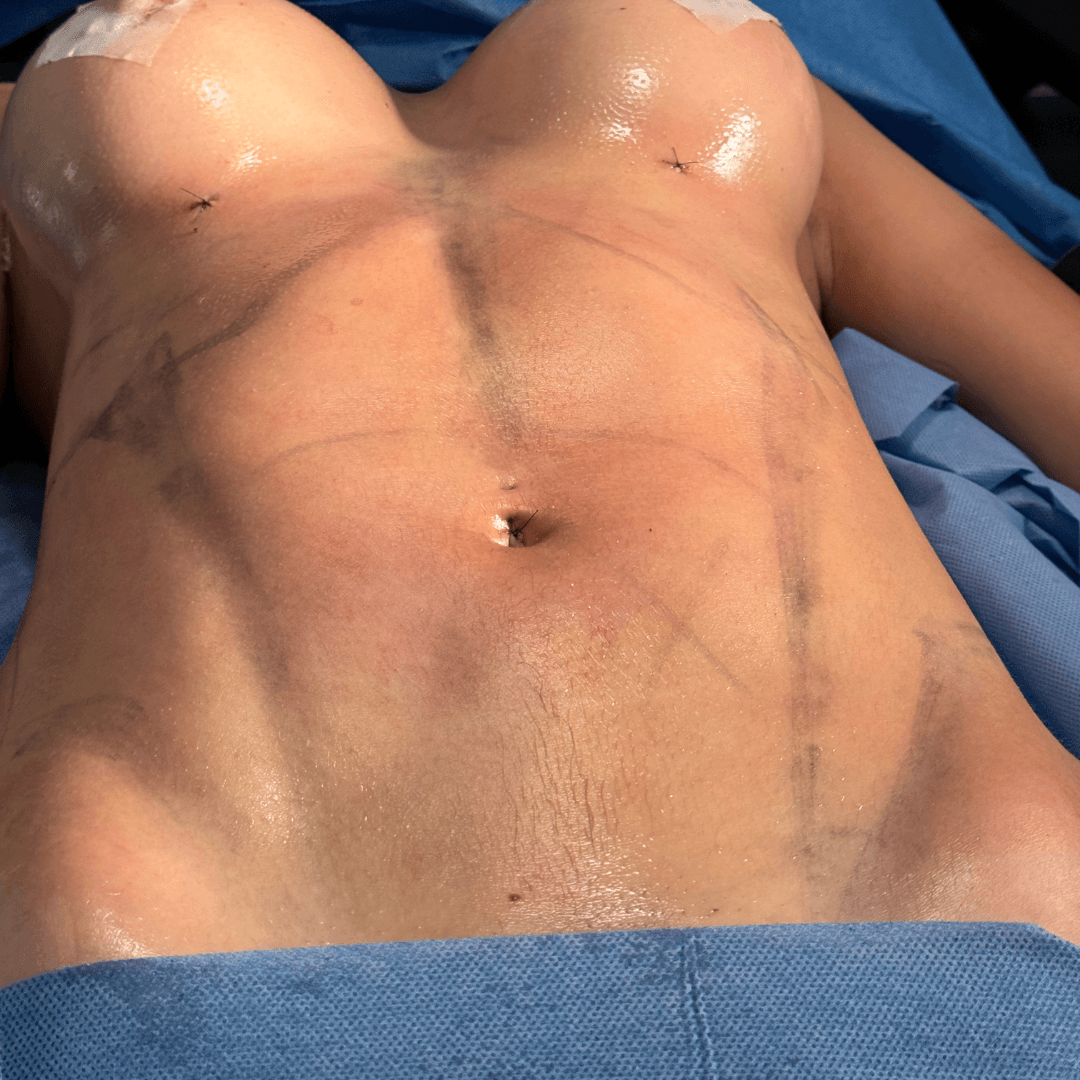

Contorno corporal y Lipo HD

Cirugia de contorno corporal avanzada y liposuccion de alta definicion, enfocada en mejorar proporciones y definir la silueta de forma natural.

Lipoescultura 360 y marcacion HD

Ver mas